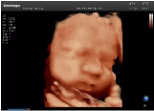

4容積探頭

積探頭是在二維圖像的基礎(chǔ)上,將連續(xù)采集的空間分布位置,經(jīng)過計算機重建算法,從而獲得完整的空間形態(tài)。

適用于:胎兒面部、脊柱和肢體等。

優(yōu)勢特點:快速獲取、掃查連續(xù)均勻、解剖結(jié)構(gòu)顯示為容積數(shù)據(jù)、準(zhǔn)確進行容積測量。